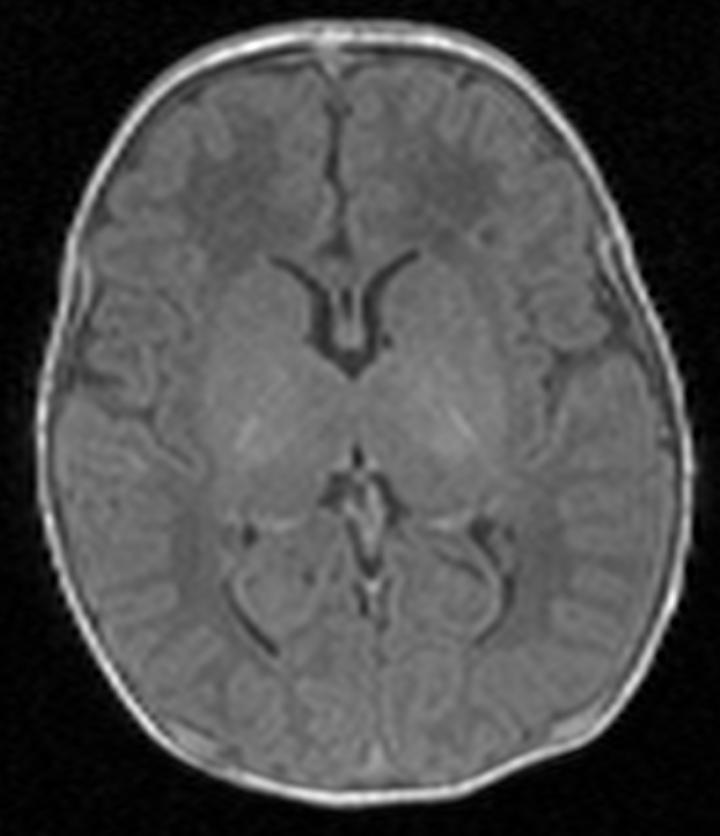

Scan One -- Healthy Brain

image: Scan one shows the brain of a healthy baby, while scan two shows that of a baby with brain damage. Compared to scan one, scan two shows abnormal brightness in the deep nuclei (in the centre of the brain), which indicates damage. view more

Credit: Imperial College London

Any child suspected of having some type of damage is given an MRI scan shortly after birth. This allows doctors to look at black and white pictures of the brain see if any areas of the brain look lighter than others, as this may suggest damage. Doctors then use this information to give parents an estimation of the extent of the damage, and the possible long-term disabilities their child may face.